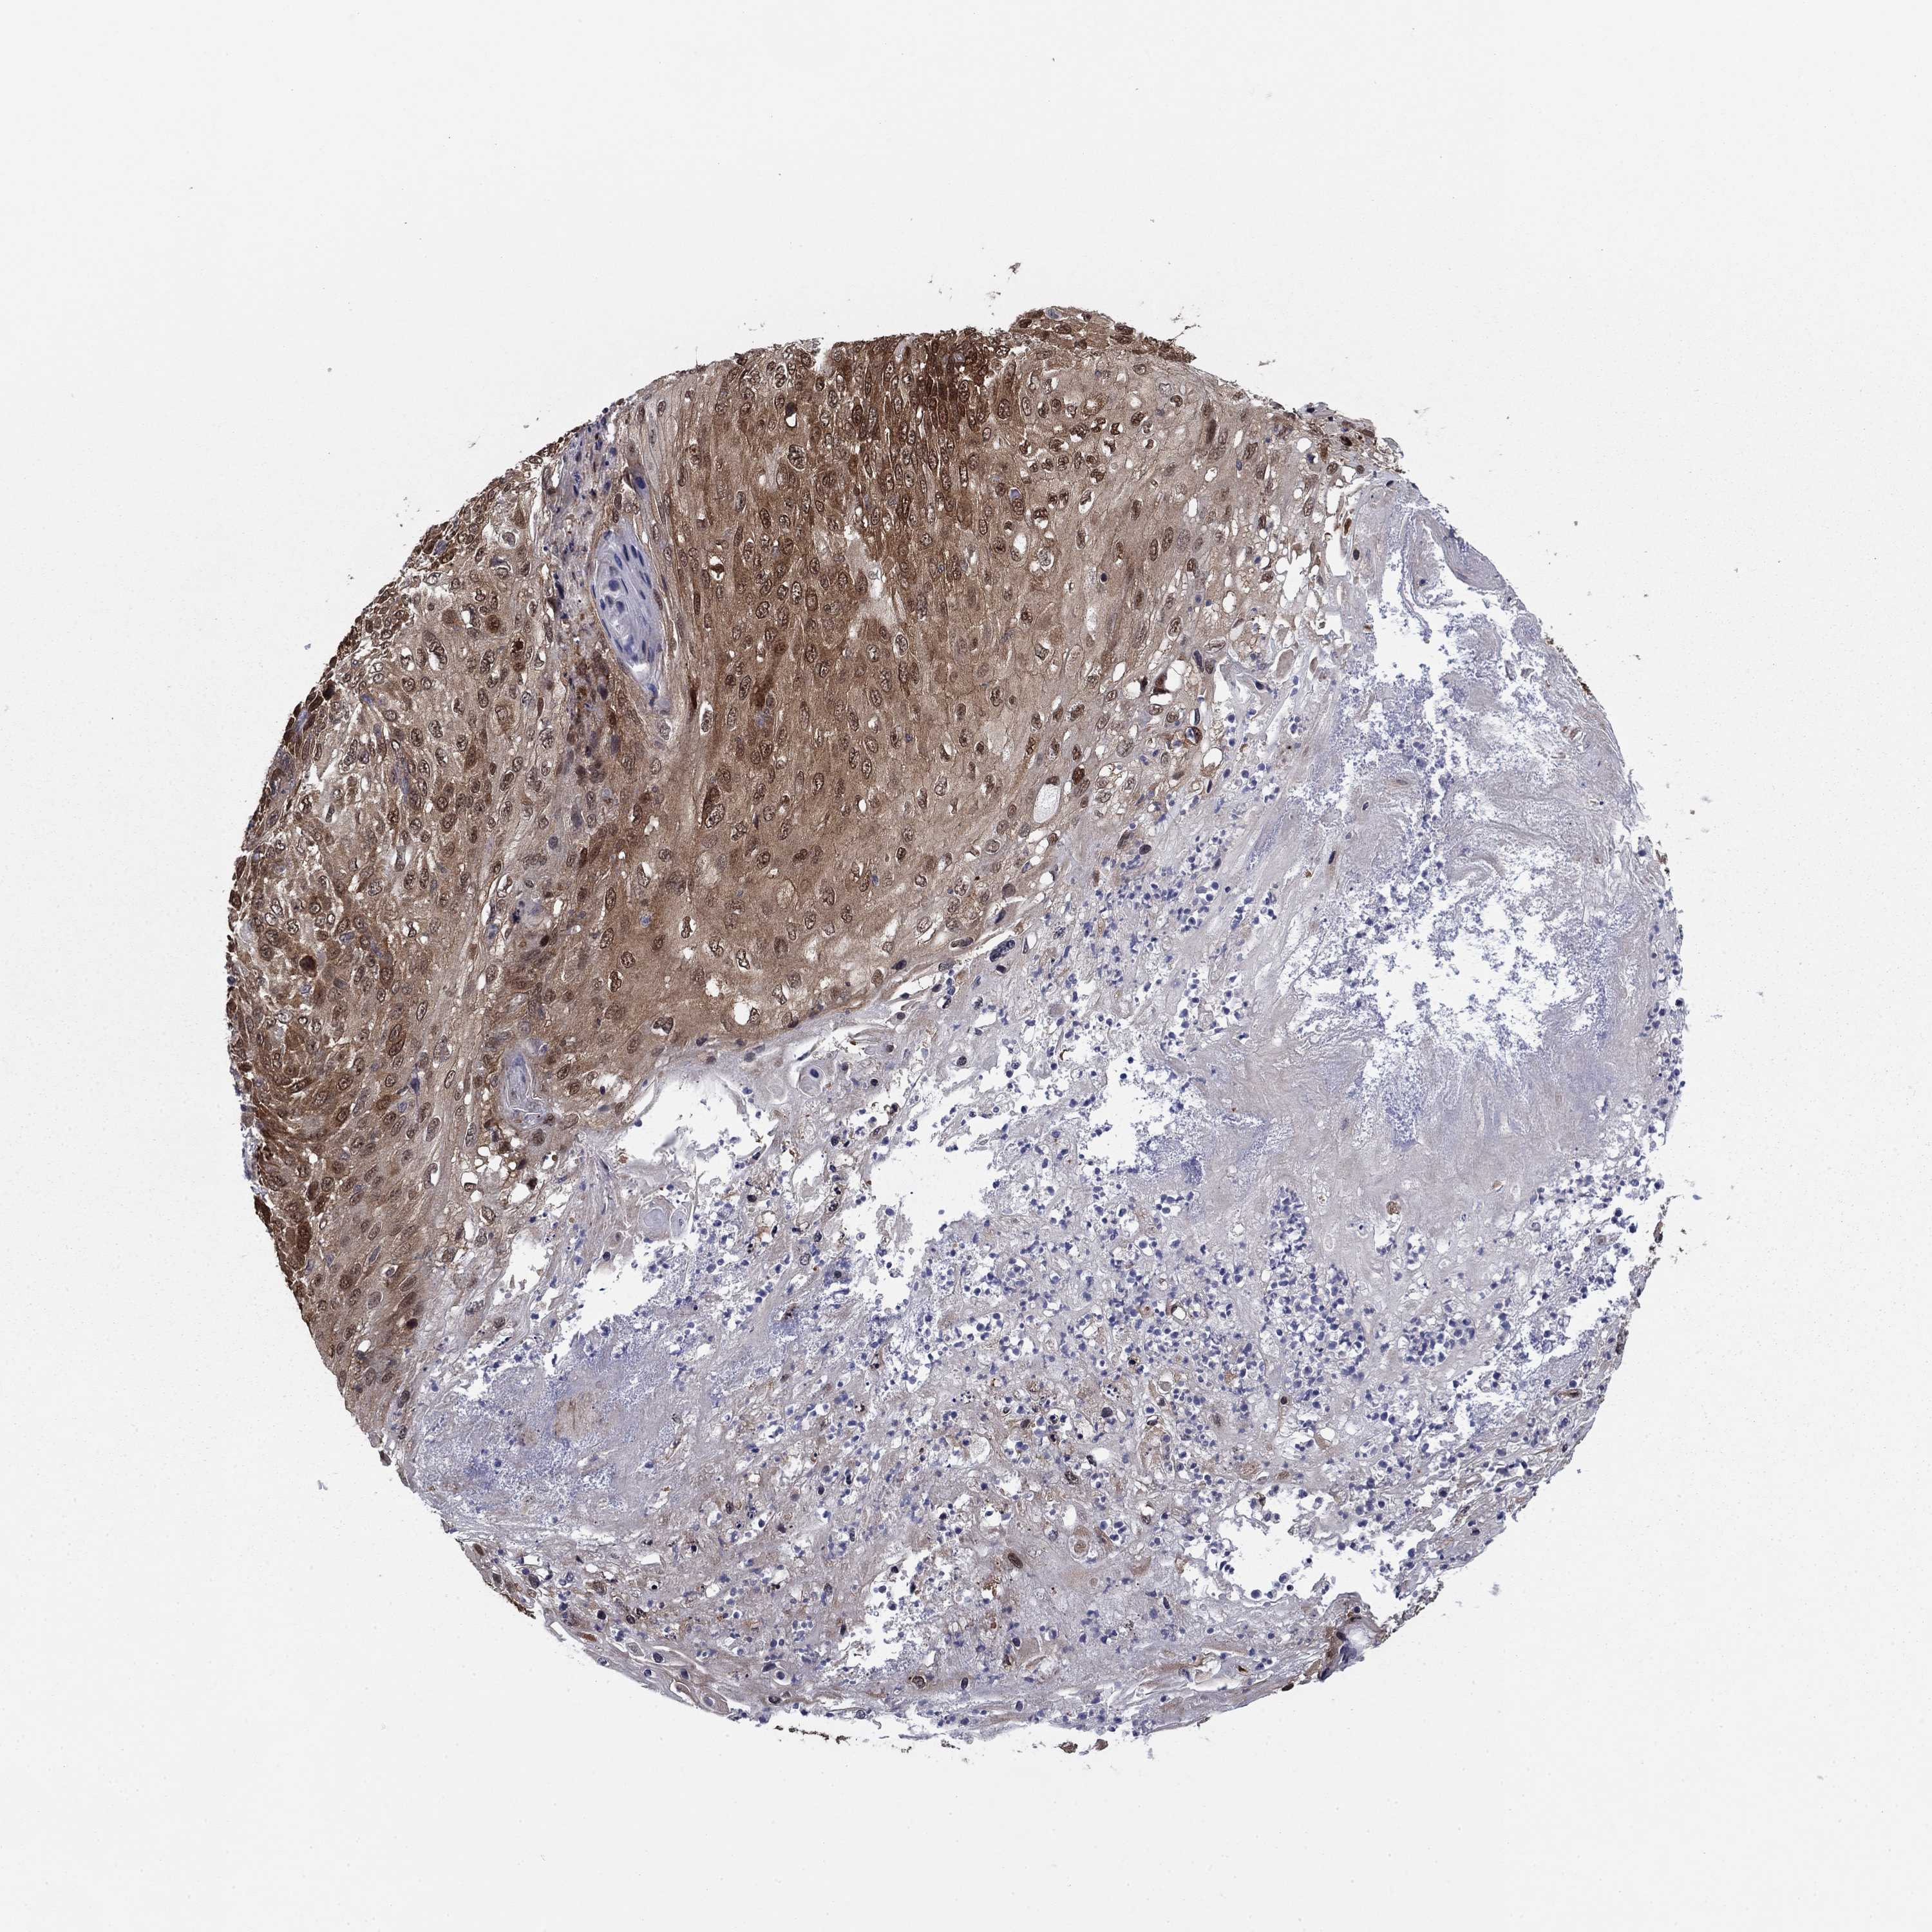

SKIN CANCER - Protein expressioni

A mouse-over function shows sample information and annotation data. Click on an image to view it in a full screen mode. Samples can be filtered based on level of antibody staining by selecting one or several of the following categories: high, medium, low and not detected. The assay and annotation is described here.

Each image is clickable and will lead to virtual microscopy that enables deeper exploration of all samples and also displays staining intensity scores, fraction scores and subcellular localization as well as patient and tissue information for each sample.

Antibody HPA006148

Antibody HPA062857

Staining

Medium

Moderate

75%-25%

Location

Cytoplasmic/membranous

Squamous cell carcinoma, NOS